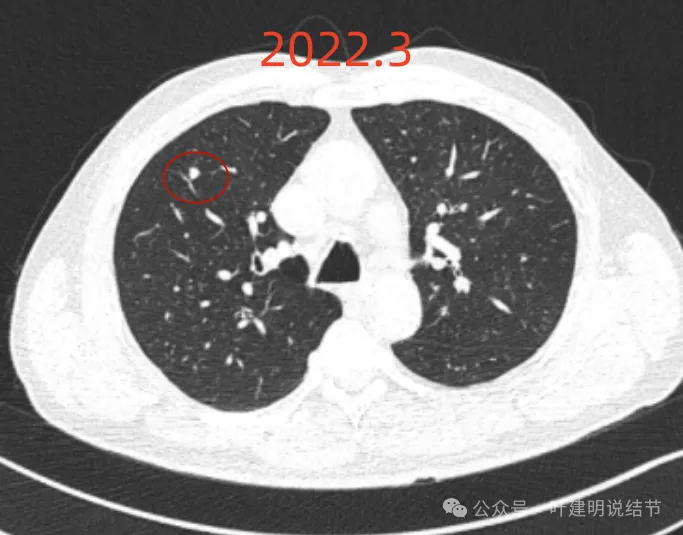

我们先来看2022年3月主要病灶的影像:

右下似见微小结节,实性,与边上小血管截面不太好区分,过小没什么临床意义,能随访。